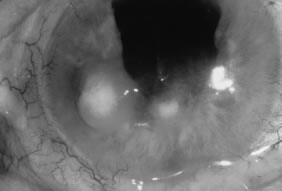

In the early stages of infection, filamentous fungi produce signs that are readily distinguishable from yeast or bacterial keratitis. The most distinctive sign is the presence of delicate, fine, feathery, opalescent, gray-white or yellow-white material in the anterior stroma, surrounded by scant cellular infiltrate or edema (Fig. 1). The epithelium may be intact. The overlying epithelium may be granular and the surface elevated and irregular in contour. Linear infiltrates typically extend into the adjacent stroma. Multiple discrete opacities may develop outside the perimeter of the principal focus of inflammation, either separated by clear stroma or linked by fine linear collections of inflammatory cells and material (Figs. 2 and 3). In the absence of inflammation in the adjacent stroma, branching hyphal fragments may be visualized by biomicroscopy (Figs. 4 and 5). Confocal microscopy may also detect hyphal elements within the stroma.28,29 Peripheral infection resembles noninfectious marginal infiltrative and ulcerative keratitis (Fig. 6). Multifocal keratitis may develop after contact lens wear or injury by multiple projectiles (Fig. 7). In the early stages, iritis is present and the intraocular pressure remains normal. Inappropriate, empirical therapy of fungal keratitis with topical fluoroquinolone or aminoglycoside antibiotics may suppress or eliminate the superficial elements but allow extension of the organisms into the stroma because these agents may possess selective antifungal activity.4,30,31

Fig. 1. Curvularia keratitis (slit-beam illumination). Note the fine feathery infiltrates extending from the central component, minimal cellular infiltrate in the adjacent stroma, and intact epithelium.